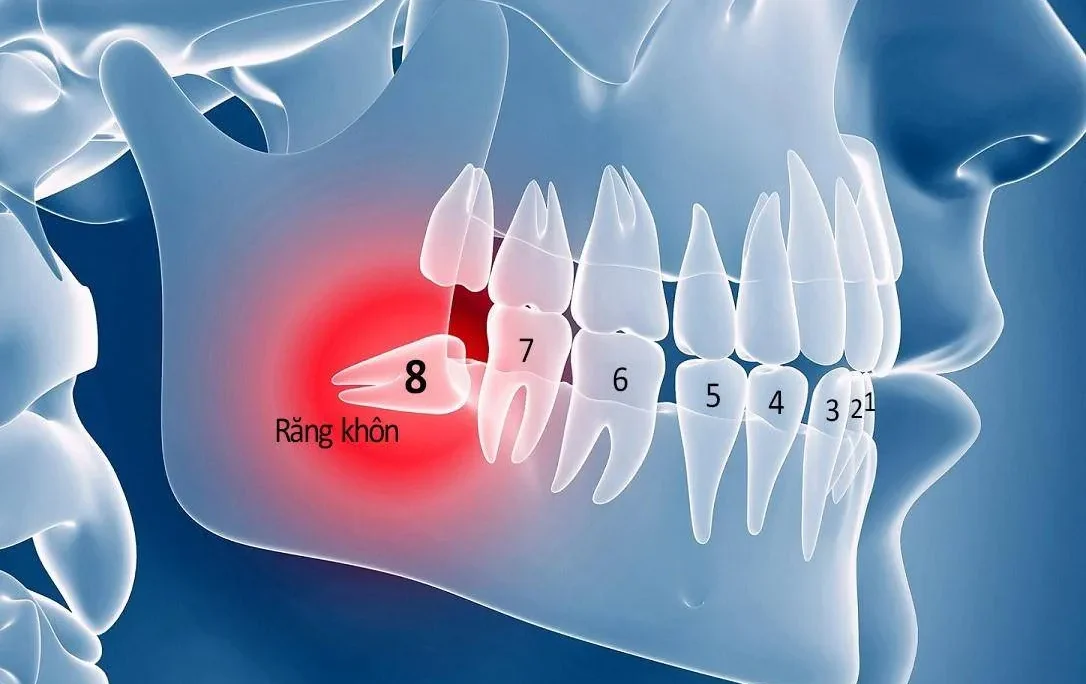

Tăng sản nướu có yếu tố di truyền, hay còn gọi là u xơ nướu di truyền, là một nguyên nhân đặc biệt dẫn đến viêm lợi phì đại. Đây là tình trạng mô liên kết của nướu phát triển quá mức do đột biến gen. Điều này thường xuất hiện từ giai đoạn mọc răng sữa. Thậm chí có thể kéo dài đến khi hoàn thiện hàm răng vĩnh viễn.

Ở giai đoạn đầu, u xơ nướu có thể không gây triệu chứng đau đớn rõ rệt. Điều này khiến người bệnh và phụ huynh khó nhận biết. Tuy nhiên, nếu không điều trị sớm, mô nướu sẽ dần bao phủ thân răng. Từ đó gây cản trở nghiêm trọng đến chức năng ăn nhai, phát âm. Cùng với đó là vệ sinh răng miệng và cả sinh hoạt hàng ngày. Trong một số trường hợp nặng, can thiệp phẫu thuật nướu là cần thiết. Thông qua đó phục hồi chức năng và thẩm mỹ.